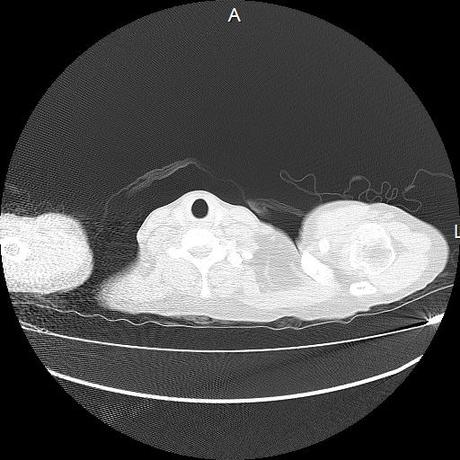

Se realiza volumen de tórax en fase simple, desde los opérculos torácicos hasta los hemidiafragmas, observándose:

Estructuras óseas sin evidencia de lesiones líticas, blásticas ni trazos de fractura. A nivel de cuerpo vertebral de T10 se observa nódulo de Schmorl que distorsiona el borde superior del cuerpo vertebral.

El parénquima pulmonar con areas parcheadas difusas en vidrio despulido combinadas con otras areas hipodensas de baja atenuación debidas a atrapamiento aéreo y engrosamiento intersticial y zonas de fibrosis de predominio en lóbulos medios e inferiores de ambos pulmones.